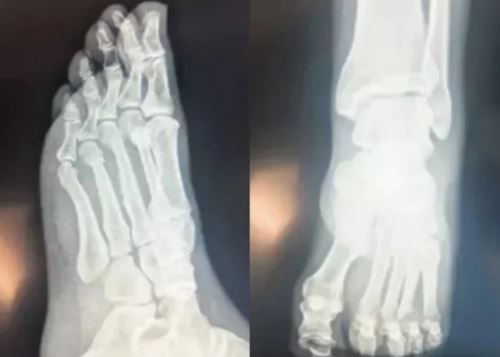

Saygı Öztürk'e konuşan Özel, ayrıca ayak röntgen filmlerini paylaştı.

Ev kazasında ayağını kıran Özgür Özel, 'ayağından vuruldu' iddialarının önüne geçemeyince ayak röntgen filmlerini paylaşarak söylentileri yalanladı.